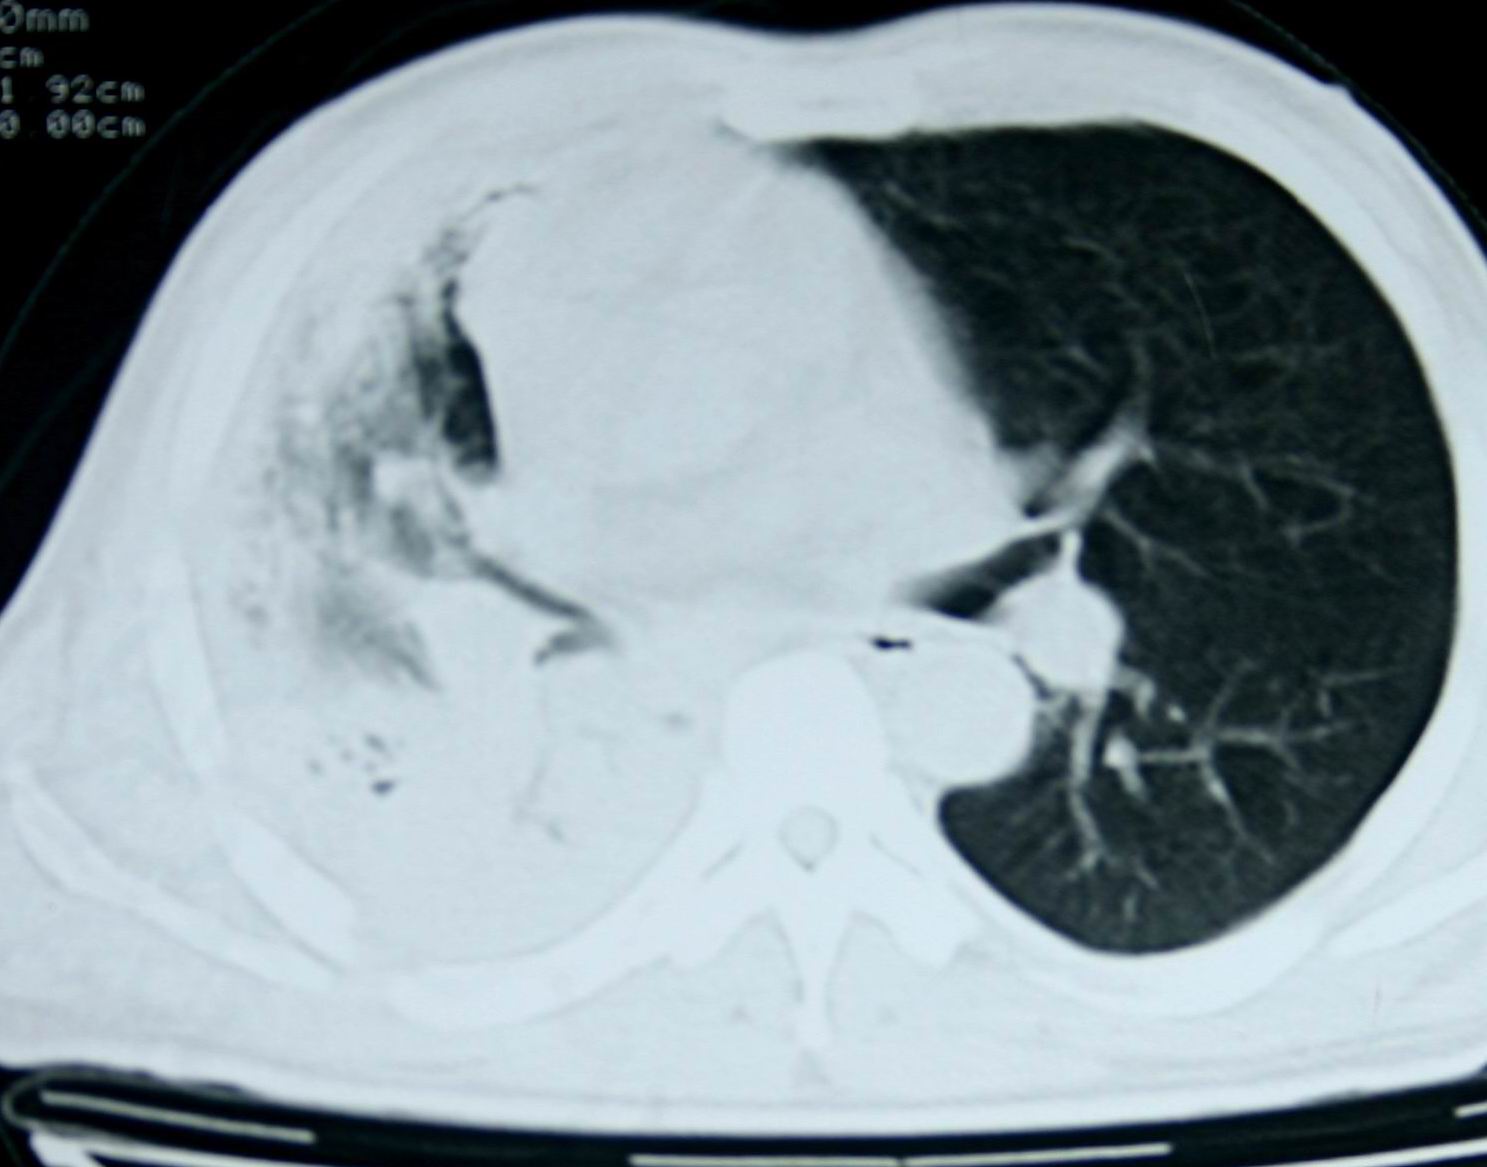

患者,男 ,48岁,反复咯血三个月,每三到五天咯一次,每次约200ml,鲜红色,无明显咳痰,咳嗽明显,无明显胸痛,无发烧,初期以抗感染、止血治疗,第一次ct报占位,支气管镜未见明显ca细,肺ca标志物、tb抗体均阴性,经过垂体后叶素、酚妥拉明、头胞他定、洛美沙星、立止血等治疗后,现病人一般情况好,停止咯血10天,咳嗽减少,咳黄脓痰,每日一次,每次30ml。现复查ct

右肺膨胀不全,纵隔右侧移位。肺内有感染,胸腔有积液。建议老片对比。

1)考虑右肺继发性肺结核合并感染。2)右侧胸腔积液+胸膜增厚。

支持:右肺膨胀不全,纵隔右侧移位。肺内有感染,胸腔有积液。建议老片对比。